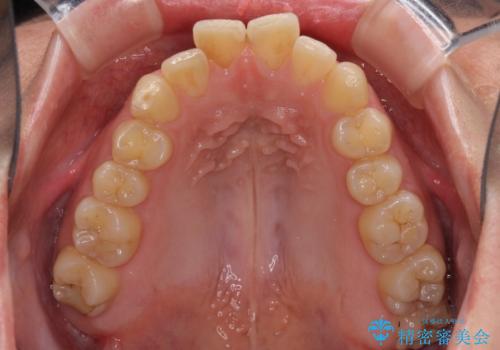

- 食いしばりが気になっていたとのことで来院された患者様です。

当初は睡眠時のマウスピースのみの製作をご希望でしたが、矯正治療の提案をしたところ、インビザラインにて矯正治療を行うこととなりました。

矯正治療中に食いしばりがより強くなることがあるため、半年に1回のペースでボツリヌストキシンによる咬合力緩和を並行して行うこととしました。

咬合力の緩和と食いしばりがちな咬み合わせが改善され、顎の負担が大幅に軽減されました。